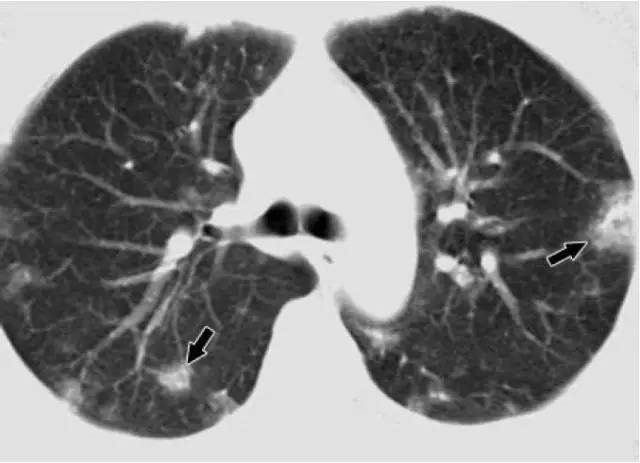

肺結節(jié)是指胸部CT 檢查影像圖片所見,肺內有直徑≤3cm的圓形、類圓形或不規(guī)則形密度增高陰影,可單發(fā)或多發(fā),邊界清晰或不清晰的病灶。

◆實性結節(jié):是指其內全部是軟組織密度的結節(jié),密度較均勻,其內血管及支氣管影像被掩蓋。

◆純磨玻璃結節(jié):是指肺內模糊的結節(jié)影,結節(jié)密度較周圍肺實質略增加,呈云霧狀淡薄影,如同磨砂玻璃一樣,但其內可以看見血管及支氣管的輪廓。

◆部分實性結節(jié)(混合性磨玻璃結節(jié)):是指其內既包含磨玻璃密度又包含實性軟組織密度的結節(jié),密度不均勻。

2.看密度:不同密度的結節(jié)惡變的風險不同,其中部分實性結節(jié)癌變的可能性最大,易形成肺腺癌,通常由小結節(jié)引起;其次是磨玻璃結節(jié),易形成肺鱗癌,高發(fā)于男性。

3.看結節(jié)特征:肺磨玻璃結節(jié)為例,通常直徑越大,其惡性可能性越大,邊緣光滑、界線清晰者良性可能性大;而邊界不規(guī)則、邊緣毛刺征、分葉征多是惡性病灶的重要征象。

4.看生長速度:良性結節(jié)生長速度較慢,病灶可穩(wěn)定2年以上;不斷增長且增長速度較快的結節(jié)惡性的幾率大。